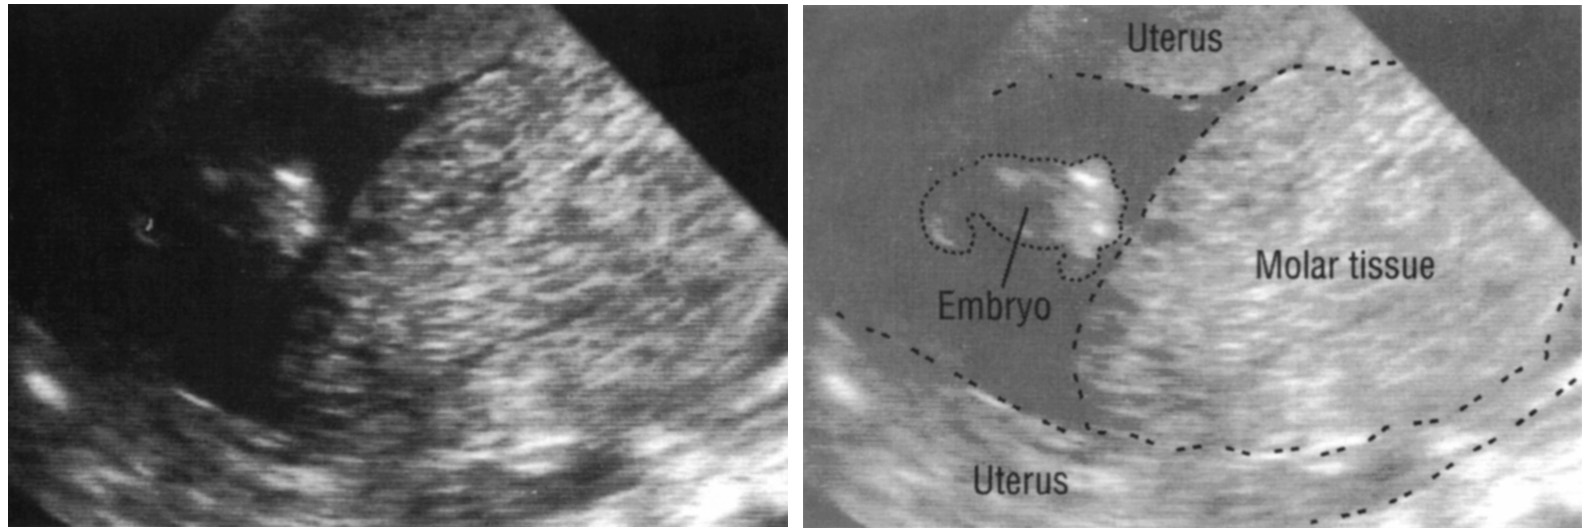

Медицина и диагностика: Инвазивный пузырный занос на УЗИ